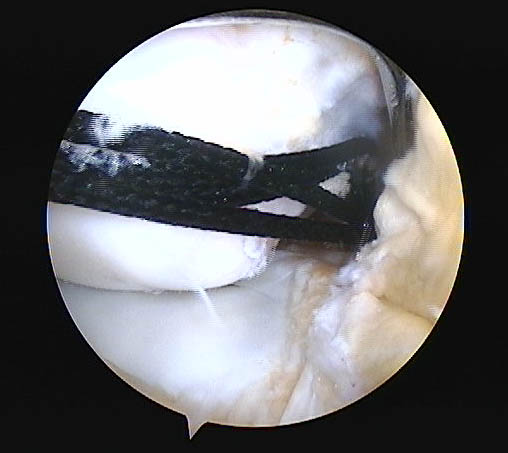

Respecto a su morfología usamos la clasificación de Lage et al.28 (Figs. 9, 10 y 11) que se distribuyeron de la siguiente manera:

-

58.6% Colgajo radial.

26.1% Fibrilada.

14.2% Longitudinal periférica.

1.1% Inestables.

Figura 11.